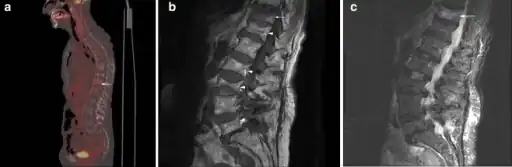

a) Sagittal fused FDG-PET/CT image demonstrates multiple compression fractures throughout the thoracic and lumbar spine b) sagittal MRI demonstrates multiple chronic compression fractures c) sagittal STIR image demonstrates mild edema in T11 compression fracture